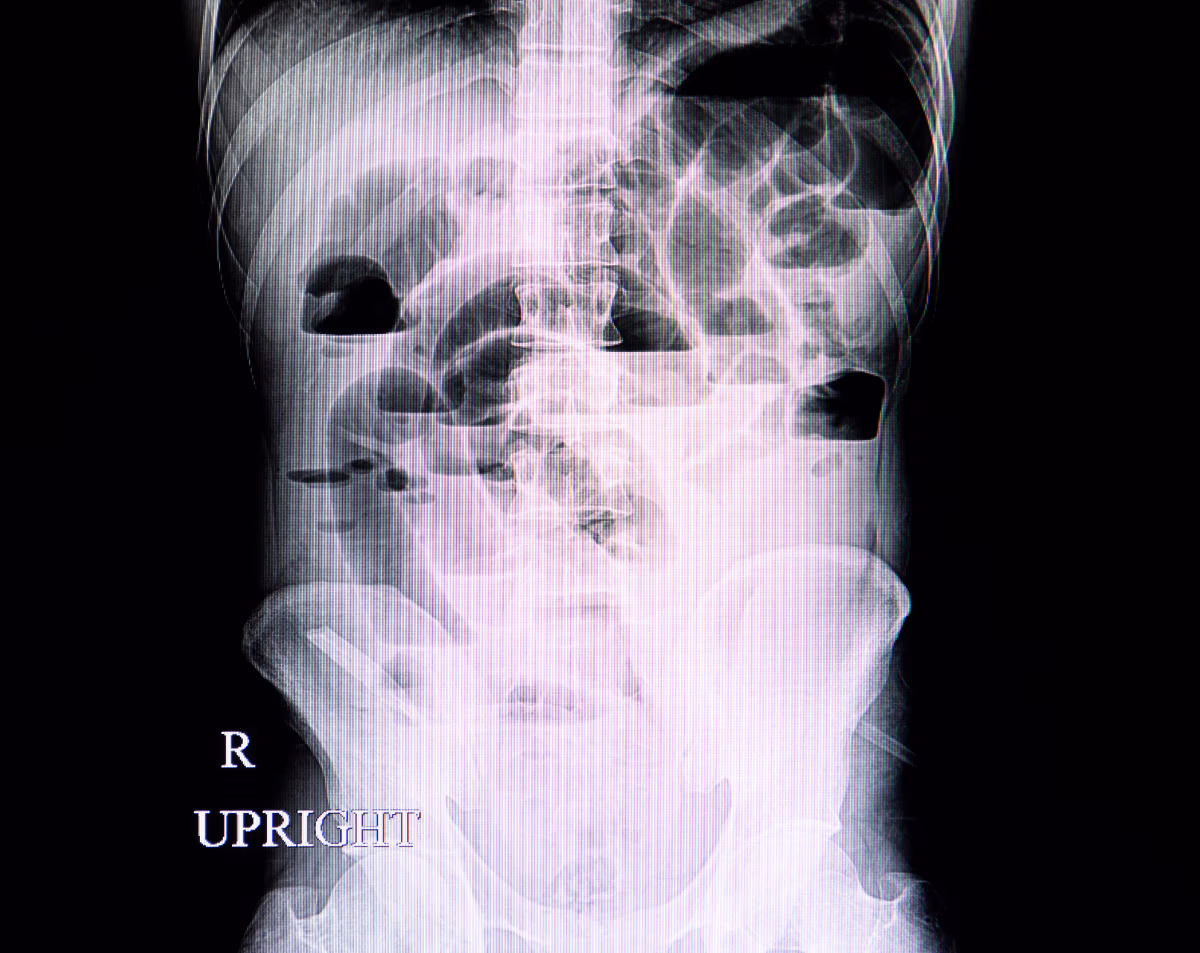

An abdominal X-ray is a quick, noninvasive imaging study that provides detailed pictures of the organs and structures within your abdomen, including the stomach, intestines, liver, kidneys, and bladder. Physicians use it to detect obstructions, abnormal masses, swallowed objects, or causes of persistent abdominal pain.

Persistent Abdominal Pain – To check for obstructions, perforations, or abnormal gas patterns.

Unexplained Nausea or Vomiting – To help identify blockages in the intestines.

Kidney Stones or Gallstones – To visualize calcifications that may cause severe pain.

Bowel Disorders – To evaluate constipation, perforations, or suspected blockages.